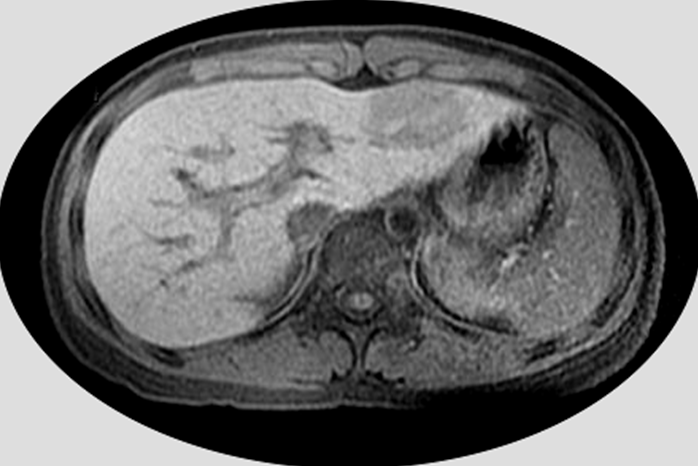

【111-1 醫學(四) 第75題】5歲男童因超音波篩檢發現腹部腫瘤,磁振造影T1加權影像如圖示,則該腫瘤位於何處?

詳解

破題關鍵

這題的關鍵在於正確辨識腹部MRI影像中的肝臟解剖位置,並根據Couinaud分段法判斷腫瘤所在的肝臟節段。圖片中可見肝臟左葉有一個明顯的腫瘤。

選項拆解